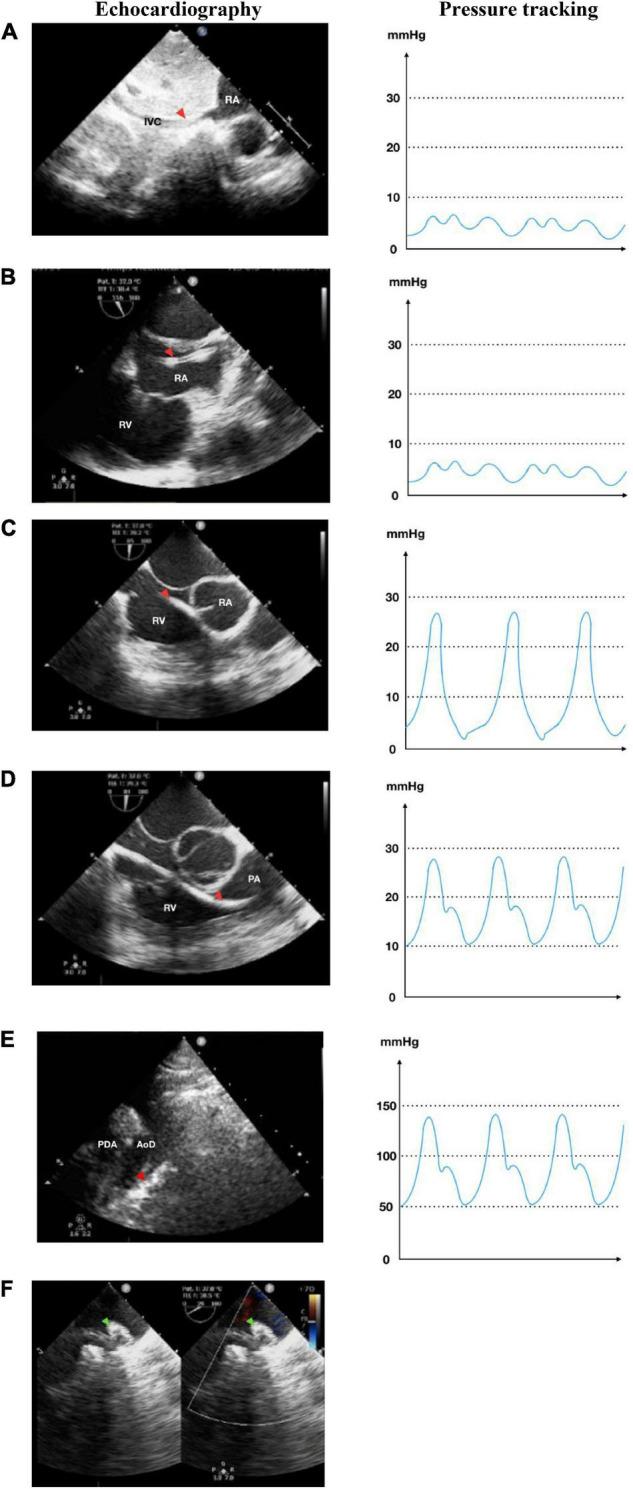

Since the first successful percutaneous closure under transesophageal echocardiographic (TEE) guidance, many centers explored transcatheter procedures without fluoroscopy. This single-center study is aimed to show the feasibility and safety of percutaneous patent ductus arteriosus (PDA) closure under echocardiography-only guidance during our 1-year experience.

Patients with PDA were recruited for percutaneous PDA closure guided by either fluoroscopy or echocardiography-only in National Cardiovascular Center Harapan Kita (ClinicalTrials.gov Identifier: NCT05321849, clinicaltrials.gov/ct2/show/NCT05321849). Patients were evaluated clinically and radiologically using transthoracic echocardiography (TTE) at 6, 24, and 48 h after the procedure. The primary endpoint was the procedural success. Secondary endpoints were the procedural time and the rate of adverse events.

A total of 60 patients underwent transcatheter PDA closure, 30 patients with fluoroscopy and 30 patients with echocardiography guidance. All patients had successful PDA closure. There were only residual shunts, which were disappeared after follow-up in both groups, but one patient with a fluoroscopy-guided procedure had moderate tricuspid regurgitation with suspected thrombus in the tricuspid valve. The procedural time was not significantly different between the fluoroscopy and echocardiography groups.